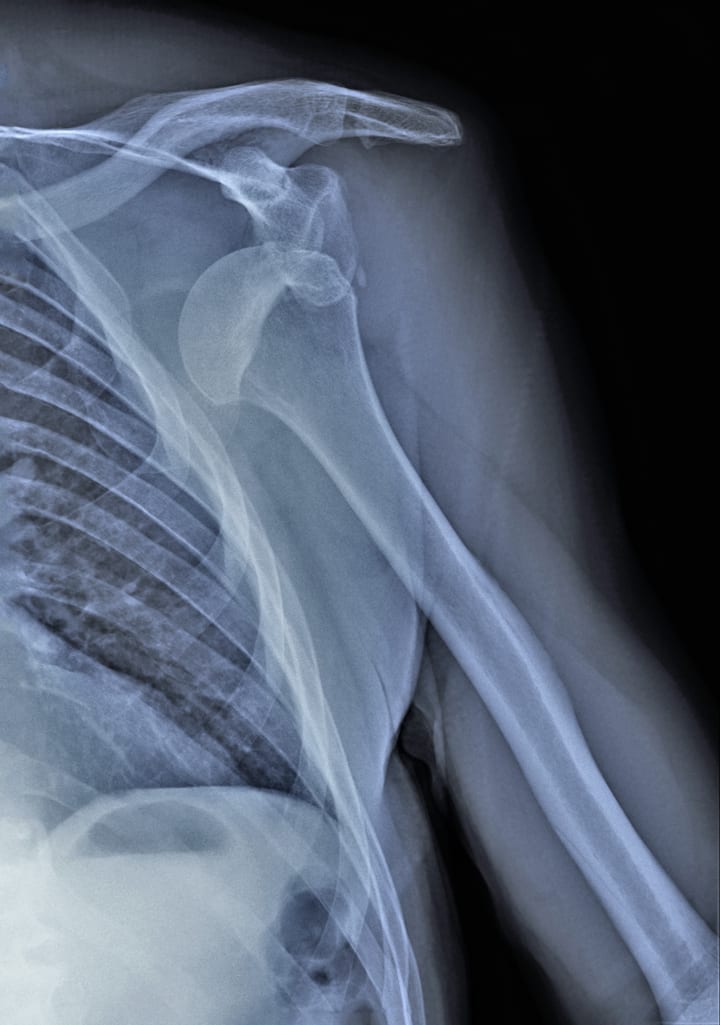

Joint instability is a common symptom of EDS, especially in the hypermobile subtype. This can lead to frequent dislocations or subluxations (partial dislocations), chronic pain, and early-onset osteoarthritis. To minimize the risk of injury, it's essential for people with EDS to be mindful of their activities and choose exercises that won't put too much strain on their joints.